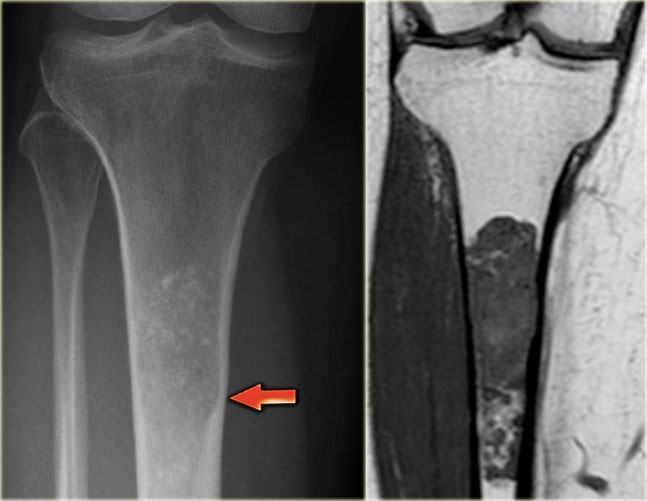

ABC (6) - atypical case

On the left two different patients with an intracortical or subperosteal osteolytic well-defined lesion in the tibia.

The lesion on the far left was thought to be an adamantinoma because of the localisation in the anterior tibial cortex.

At biopsy it proved to be an ABC.

The image on the right is an adamantinoma.